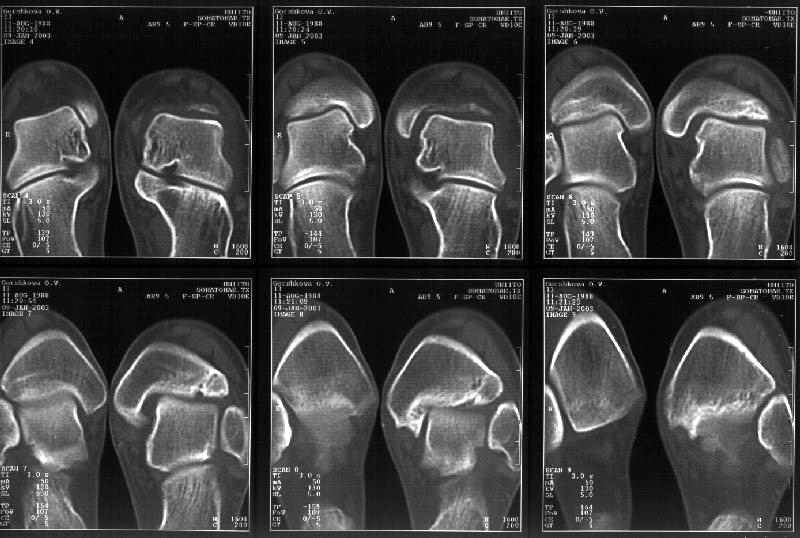

Отправитель: Alexander Chelnokov 19 Январь 2003, 22:34

Сегодня пациентке сделали сравнительную КТ. А ксиальные и Фронтальные срезы приложены. Ваше мнение?

Фронтальные

Аксиальные

Отправитель: Й. Воск 19 Январь 2003, 22:50

На КТ я попытался изобразить скромными своими способностями (А)- место перелома, (С)- нормальный суставной зазор меж тараном и тремя его маллеолами. (В)- образовавшийся в результате перелома широкий раза в три зазор, позволяющий, по-моему, сублюксацию тарана при ходьбе. В свете данных КТ, критически важных, я бы предложил вертикальную остеотомию места перелома

задне-внутренним подходом и фиксацию мед. маллеола прижатым к тарану с помощью тонкого compression screw. После этого гипсовый сапожок и немедленное расхаживание ноги.